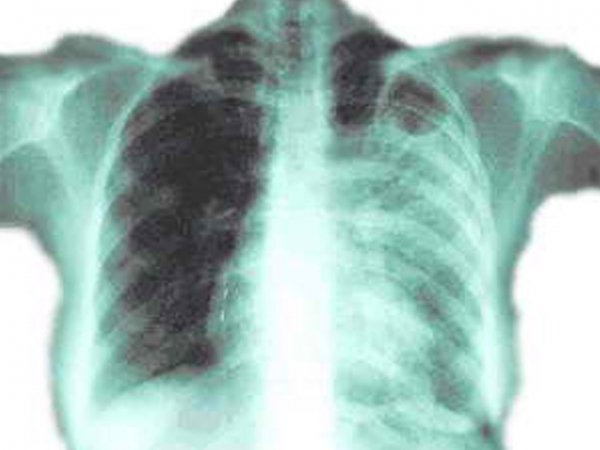

За даними МОЗ України, в нашій державі триває епідемія туберкульозу, адже щороку виявляють до 40 тис. нових хворих та майже 10 тис. помирає від різних форм туберкульозу.

В нашій області на обліку протитуберкульозної служби перебуває понад 15 тис. волинян; майже 1 тис. - хворіє активними формами туберкульозу; щороку помирає від небезпечної хвороби від 150 до 180 хворих.

На фоні деякого зниження рівня захворюваності на туберкульоз органів дихання протягом минулого року, залишається ще високою кількість хворих з підтвердженим бациловиділенням. Надто прикро, коли хворіють діти (щорічно реєструється в межах 10 - 15 хворих серед дітей до 17 років).